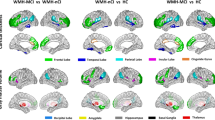

Voxel-wise analyses of GM yielded a wide-spread GM decrease in CI compared to CP most pronounced in deep GM. Adjusting for EDSS weakened but did not fundamentally change the result (Fig. 3a, b). Regional analyses of cortical thickness revealed wide-spread cortical thinning in the CI group which was only slightly weakened after adjusting for EDSS (Fig. 4a, b). Aiming at parameters exerting an independent effect on CI, we repeated the voxel-wise and surface-based analyses after inclusion of image-based covariates. In the voxel-wise analyses, thalamic atrophy remained significant after inclusion of cortical atrophy (Fig. 3c) but almost disappeared after inclusion of WML volume (Fig. 3d). Reduced cortical thickness lost significance primarily in the occipital and parietal cortex after inclusion of either thalamic volume or WML, whilst large areas of reduced cortical thickness in frontal and anterior temporal areas remained significant (Fig. 4c, d). To better visualize areas with most pronounced cortical thinning, we lowered the statistical threshold to a p value of < 0.05 family-wise error corrected at the voxel level revealing eight areas: bilateral parahippocampal gyrus (1 and 2), left superior frontal gyrus (3), rostral middle frontal gyrus (4), left middle superior temporal gyrus including transverse temporal gyrus (5), right precentral gyrus (6), right middle temporal gyrus (7), and right supramarginal gyrus (8).

Group comparison of grey matter images. Group comparison of grey matter images between cognitively impaired and cognitively preserved patients with multiple sclerosis after adjusting for different sets of covariates. a Significant grey matter loss in cognitively impaired compared to cognitively preserved patients is depicted adjusting for age, sex, and TIV; b after additionally adjusting for disability; c after additionally adjusting for cerebral cortex; d and after additionally adjusting for white matter lesion volume. Slices are projected onto the Montreal Neurological Institute (MNI) template. Coordinates are indicated for coronal (y), sagittal (x), and axial slices (z). Statistical parametric maps are thresholded at p < 0.05 corrected (threshold-free cluster enhancement). Effects are scaled from dark red to light yellow with the latter indicating more grey matter loss. EDSS Expanded Disability Status Scale, lgWML decadic logarithm of white matter lesion volume, TIV total intracranial volume

Group comparison of cortical thickness. Group comparison of cortical thickness between cognitively impaired and cognitively preserved patients with multiple sclerosis after adjusting for different covariates. a Significant cortical thinning in cognitively impaired compared to cognitively preserved patients with multiple sclerosis is depicted after adjusting for age, sex, TIV; b after additionally adjusting for disability; c after additionally adjusting for thalamic volume; d and after additionally adjusting for white matter lesion volume. The left and right hemispheres are shown separately. Increasing significance is color-coded from dark red to light yellow, the latter indicating more cortical thinning. The statistical threshold was set to p < 0.05 corrected (threshold-free cluster enhancement). EDSS Expanded Disability Status Scale, lgWML decadic logarithm of white matter lesion volume, TIV total intracranial volume

With regard to the cerebral cortex, we observed wide-spread thinning in patients with CI compared to patients with CP. Although to a lower extent, we could relate cortical regions (primarily temporal and frontal lobe regions) more specifically to CI by correction for WML volume or overall disability (i.e., EDSS). The resulting effect was very robust but not in the order of magnitude of thalamic atrophy or WML. In MS patients in stages as early as our cohort, cortical atrophy was related to CI in only few studies [9, 46], whilst this effect seems to become more robust in later stages [4, 9, 47, 48]. Of note, a recent study demonstrated reduced cortical GM volume as the only significant MRI predictor of cognitive decline over a period of 5 years in a cohort at a later stage (compared to our cohort) with a mean symptom duration of 15 years at baseline [29]. We, therefore, speculate that the effect of cortical thinning on CI in MS is smaller in the early stages and comes more and more into play in later stages.